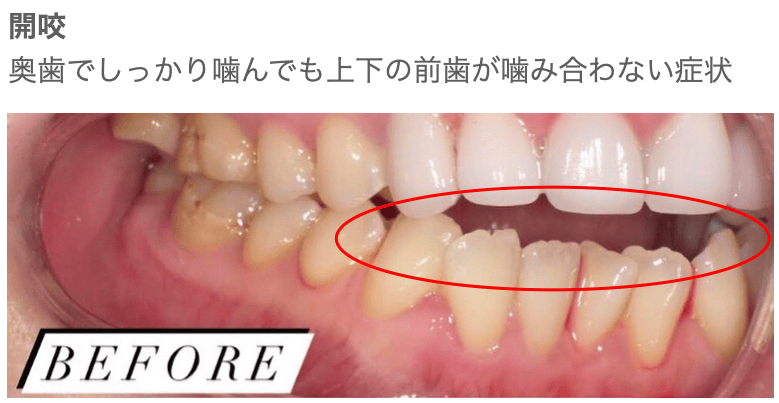

Case014

「開咬」の方の審美治療です。

「開咬」とは文字通り、しっかり噛んでも前歯が咬み合わず、隙間ができてしまう咬みあわせのことをいいます。

この状態だと、上の歯が出ていなくても、出ているように見えてしまったり、いつでも口が開いているように見えるため、口元の洗練さが落ちてしまいます。

今回はセラミック矯正で治療させて頂きました。

笑顔の時に口が開いているように見えてしまっていましたが、洗練された笑顔になりました。

担当 理事長 佐藤悠野